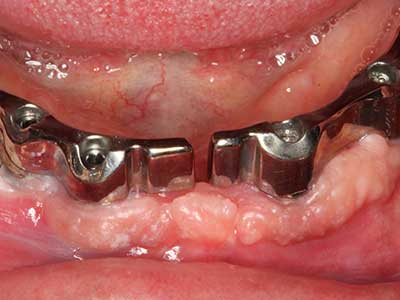

Индикация: Костно разделяне/ шиниране?

Костната тъкан е не само минерализирана структура, тя съдържа и съществено количество колагенови влакна. Това означава, че тя има не само добра компресивна сила, но и известна степен на гъвкавост, която може да се възприеме като предимство при извършване на костна аугментация. В класическата процедура по разширяване чрез костно разделяне, атрофиралият алвеоларен гребен е разделен надлъжно и внимателно разширен след достигане на подходящата остеотомна дълбочина (Фиг. 13-16), в идеалния случай без допълнително отстраняване на периостеума (Brugnami, Caiazzo et al. 2014, Stricker, Fleiner et al. 2014). Системите с винт и пластини с увеличаване на разстоянието при разширяване са доказали ефективността си при разделяне на двете костни ламели, оставайки под прага на фрактурите. В общи линии, оставащата ширина на костта от поне 3–4 mm е задължителна (Chiapasco, Zaniboni et al. 2006), за да се гарантира добра гъвкавост и достатъчно костно покритие за бъдещото поставяне на импланти. Ако е необходимо, вертикалната остеотомия на едната или двете страни може да подобри гъвкавостта. Комбинацията с допълнителни техники за аугментация, особено в букалната страна, е описана като алтернатива на класическата техника.

Процедурата по разделяне е атравматична и няма голяма загуба на пространство, използвайки пиезотриони, и няма значителна разлика между импланти в разделени челюсти и импланти в алвеоларния гребен без костен дефицит (Chiapasco, Zaniboni et al. 2006, Danza, Guidi et al. 2009). Въпреки това, важно е да има достатъчно и продължително охлаждане, особено при ограничено и дълбоко разделяне, за да се избегне термичен стрес в апикално-остеотомните зони.